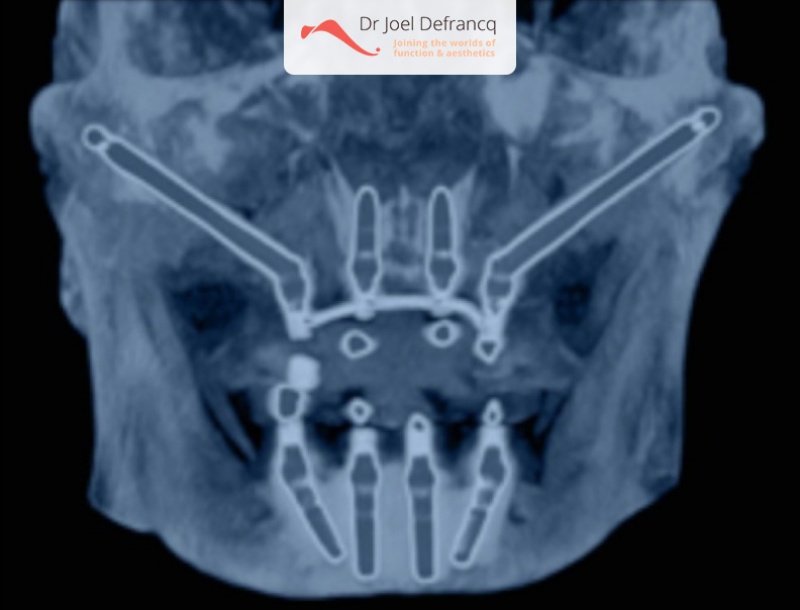

In de jaren ’90 startte P.I. Bränemark uit Zweden met een techniek waarbij het bot dat de jukbeenderen vormt, gebruikt wordt als ankerpunt voor het plaatsen van dentale zygoma-implantaten. In het jaar 2003-2004 werden hiervan resultaten en data gepubliceerd die gelijkaardige succesratio’s vertoonden als bij conventionele implantaten.De techniek van de plaatsing van zygoma-implantaten werd gedurende de laatste twintig jaar ontwikkeld en is als zodanig niet echt een punt van discussie. Er wordt niet gerekend op verankeringsmogelijkheden van het alveolaire kaakbot, zoals bij de conventionele implantaten. De zygoma implantaten groeien enkel vast ter hoogte van de jukbeenderen. Deze implantaten zijnl langer (tussen 3,5 en 5 cm) dan de reguliere implantaten (tussen 0,7 en 1,5 cm).

Heel vaak kan één zygoma-implant aan elke kant gecombineerd worden met reguliere implantaten in het gebied van de voortanden. In meer extreme gevallen worden langs elke zijde 2 zygoma implantaten geplaatst en worden eveneens dadelijk belast.

Vooraleer de operatie plaatsvindt, nemen we een extended i-cat). Deze laat ons toe de beenderige structuren, in het bijzonder de jukbeenderen, driedimensionaal te bestuderen. Zygoma-implantaten worden onder algemene anesthesie geplaatst.

Optie 1: We plaatsen vier zygoma-implantaten in de totale en extreem atrofische bovenkaak (aangezien bot ontbreekt voor reguliere implantaten), gevolgd door een vaste suprastructuur (tanden) binnen de paar dagen. Een extra regulier implantaat ter hoogte van de voortanden is altijd aan te raden, omwille van een betere stabiliteit. Dit kan later veel klachten voorkomen.Optie 2: We plaatsen twee zygoma-implantaten in het gebied van de tweede voorkiezen en drie tot vier reguliere implantaten ter hoogte van de voortanden. Deze optie wordt ook gevolgd door een vaste suprastructuur (tanden) binnen de paar dagen.

Er is inderdaad meestal nog wat bot aanwezig in het voorste deel van de bovenkaak recht onder het neusgebied. Indien er enkele (twee tot vier) reguliere implantaten kunnen worden geplaatst in het gebied van de voortanden, zal dr. Defrancq dit altijd doen. De sinussen zijn in de meer achtergelegen delen van de bovenkaak gelegen, en ten gevolge van de sinusuitbreiding is er daar vaak niet genoeg bot aanwezig. Dr. Defrancq plaatst daar twee zygoma-implantaten. Een rechtstreekse belasting volgt altijd op de ingreep en de patiënt heeft binnen een week vaste porseleinen of chroom-kobalt tanden.